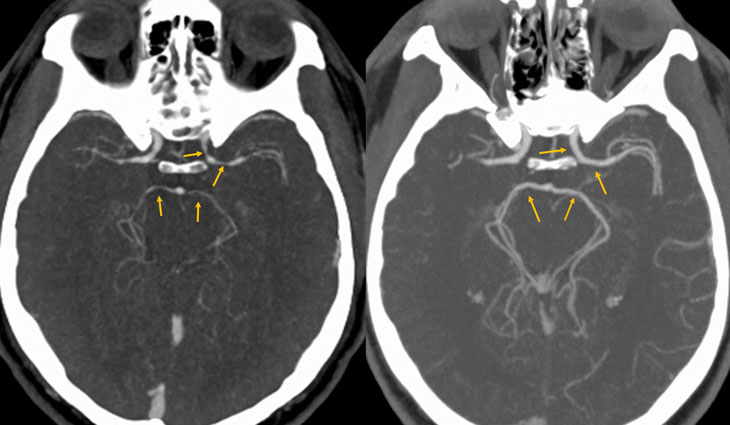

Known as the Carolina Reaper, the chili can constrict arteries in the brain